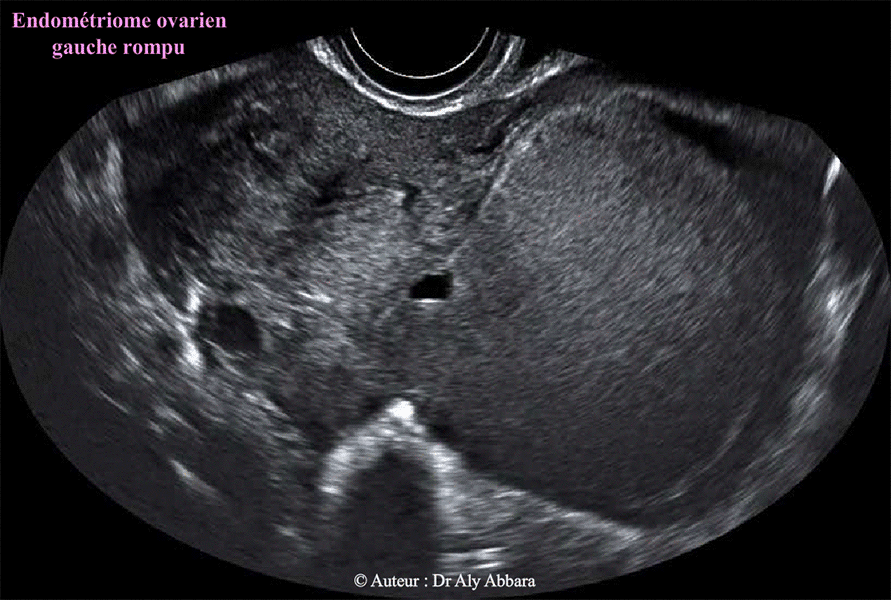

• Images échographiques montrant l'aspect ultra-sonore d'un endométriome (kyste endométriosique) ovarien gauche de 128 cm3 de volume.

Il s'agit d'une formation kystique uniloculaire mesurant (6

6 x 64 x 58 mm) ; à paroi régulière, de 1 à 2 mm d'épaisseur, sans végétation endophytique.

Le contenu du kyste est liquidien, homogène

, hypo-échogène correspondant cliniquement à un liquide formé du sang lysé, concentré et épaissi, prenant un aspect chocolatoïde (comme le chocolat fondu), qu'on voit normalement dans les kystes endométriosiques (endométriomes).

L'épanchement péritonéal

possède les mêmes caractéristiques échographiques du contenu de cet endométriome ; cliniquement, il s'agit d'une partie du contenu liquidien chocolaté qui a échappé du kyste suite à sa rupture spontanée.